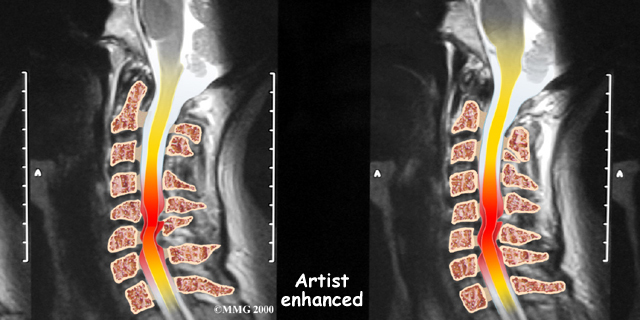

If more information is needed, your doctor may order a magnetic resonance imaging (MRI) scan. The MRI machine uses magnetic waves rather than X-rays to show the soft tissues of the body. This test gives a clear picture of the spinal cord and can show where it is being squeezed. This machine creates pictures that look like slices of the area your doctor is interested in. The test does not require any special dye or a needle.

Soft Tissues